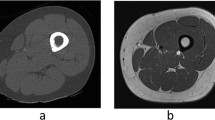

A method is proposed for 3D segmentation and quantification of the masseter muscle from magnetic resonance (MR) images, which is often performed in pre-surgical planning and diagnosis. Because of a lack of suitable automatic techniques, a common practice is for clinicians to manually trace out all relevant regions from the image slices which is extremely time-consuming. The proposed method allows significant time savings. In the proposed method, a patient-specific masseter model is built from a test dataset after determining the dominant slices that represent the salient features of the 3D muscle shape from training datasets. Segmentation is carried out only on these slices in the test dataset, with shape-based interpolation then applied to build the patient-specific model, which serves as a coarse segmentation of the masseter. This is first refined by matching the intensity distribution within the masseter volume against the distribution estimated from the segmentations in the dominant slices, and further refined through boundary analysis where the homogeneity of the intensities of the boundary pixels is analyzed and outliers removed. It was observed that the left and right masseter muscles’ volumes in young adults (28.54 and 27.72cm3) are higher than those of older (ethnic group removed) adults (23.16 and 22.13cm3). Evaluation indicates good agreement between the segmentations and manual tracings, with average overlap indexes for the left and right masseters at 86.6% and 87.5% respectively.

Ng HP, Ong SH, Hu Q, Foong KWC, Goh PS, Nowinski WL: Muscles of mastication model-based MR image segmentation. Int J Comput Assis Radiol Surg 1(3):137–148, 2006

Ng HP, Ong SH, Foong KWC, Goh PS, Nowinski WL: Masseter segmentation using an improved watershed algorithm with unsupervised classification. Comput Biol Med 38(2):171–184, 2008